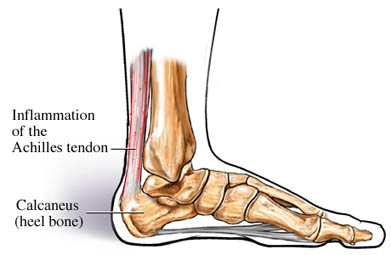

Så, då har man varit hos läkaren och kollat hälsenan med ultraljudsundersökning. Den var svullen 9 mm tjock, skall inte vara över 6 mm. Det fanns lite blodkärl i den som ”hjälper svullnaden”, men han tyckte inte att det var så mycket så att han behövde injicera medicin.

Det kan dock ta väldigt lång tid att bli av med detta så ge de några månader till och fortsätt med tåhävningar var rådet. Har det inte blivit bättre efter nyår kan jag höra av mig igen!